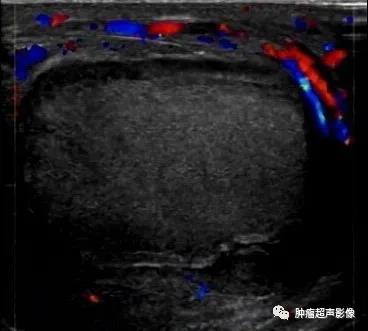

睾丸炎性坏死(67,手术及病理证实):睾丸未见血流,周边阴囊壁增厚,血流增多。